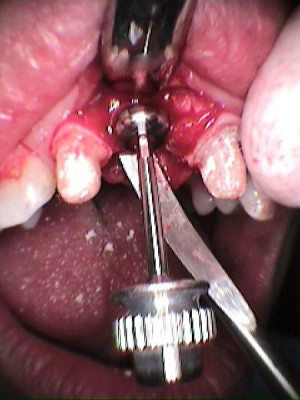

Secuencia de colocación de implante

Se coloca poste de impresión